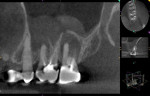

The patient returned 6 months later for a follow-up CBCT scan (Figure 4). The scan revealed near-complete resolution of the periapical lesion and mild residual mucosal thickening of the sinus floor. At this follow-up visit the patient reported her dental and sinus symptoms had resolved.